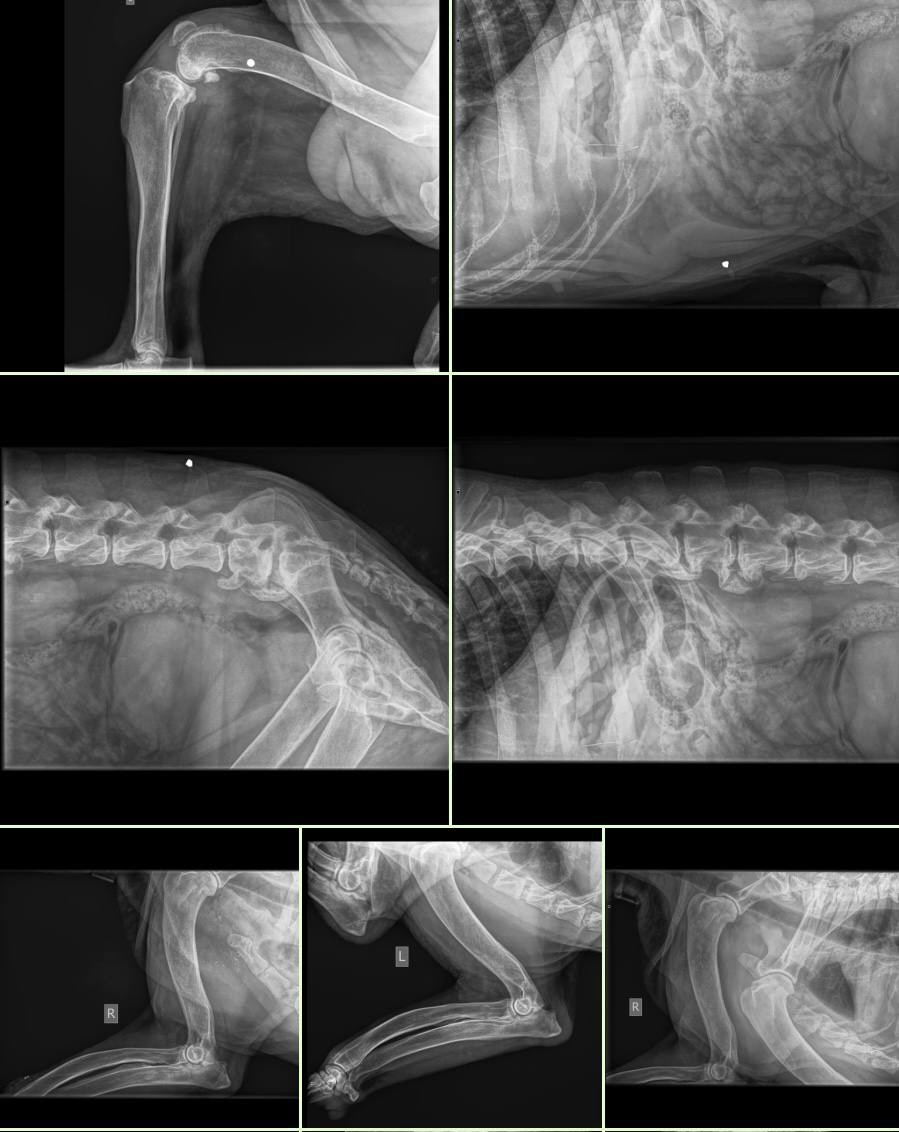

День 1-й. По возрасту врачи определили, что, конечно Барсу не 4 и не 5 лет. Он очень пожилой, а его тело на рентгене показало дроби в мягких тканях. Когда-то в него стреляли. Но это не самое страшное, с этим живут, а пули так и сидят в мягких тканях.

День 2-й. Консультация невролога вчера показала наличие спондилеза на всех участках позвоночника, более выражено в крестцово- поясничном отделе. Также, предположительно новообразование в головном мозге. Для более точного диагноза необходимо МРТ, но в данный момент Барс в тяжелом состоянии и это не представляется возможным.

Точная причина его ухода останется неизвестной. Врачи предполагали либо тяжёлую форму спондилёза, либо опухоль головного мозга, на что указывали резко усилившиеся обильные гн'ойные выделения из носа

Это его последние съёмки...